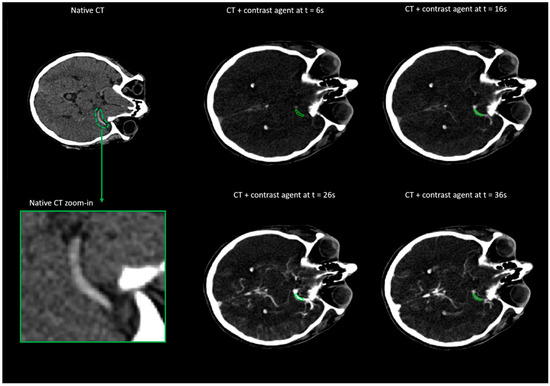

- Santos, E.M.M.; d’Esterre, C.D.; Treurniet, K.M.; Niessen, W.J.; Najm, M.; Goyal, M.; Demchuk, A.M.; Majoie, C.B.; Menon, B.K.; Marquering, H.A.; et al. Added value of multiphase CTA imaging for thrombus perviousness assessment. Neuroradiology 2018, 60, 71–79. [Google Scholar] [CrossRef]